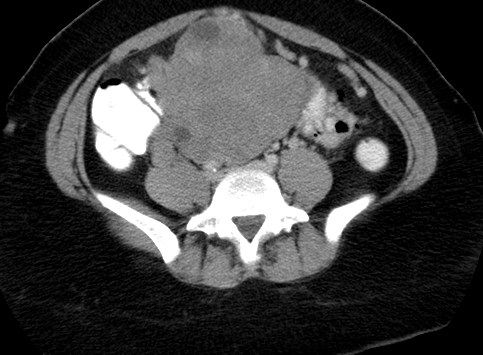

Adenomatoid uterine tumors are rare, and their appearance on medical imaging modalities is not well established We present a case of an adenomatoid uterine tumor reviewing a unique sonographic presentation, magnetic resonance imaging (MRI), gross surgical appearance of the tumor, and microscopic pathology imagesUnlike ultrasound and magnetic resonance imaging (MRI), computed tomography (CT) is uterine arteries, branches of the anterior division of the internal iliac arteries (Fig 1) Yitta et al 13 described a fourth heterogeneous and multifocal enhancement pattern of the entire myometrium (Fig 4 and 10) Although ultrasound (US) is almost always the first modality used in the radiologic workup of endometrial disease, findings at sonohysterography, hysterosalpingography, magnetic resonance imaging, and computed tomography are often correlated with US findings

Muscular hyperplasia and hypertrophy cause focal or diffuse myometrial thickening and globular uterine enlargement, often with thin "venetian blind" shadows The combination of these findings results in a heterogeneous myometrium, with blurring of the endometrial borderUnicornuate uterus is presented Abdominal and pelvic ultrasound revealed ahypertrophied right kidney measuring 130 cm, anormal right ovary, and absent left kidney and ovary Computerized tomography of the abdomen and pelvis confirmed absence of the left kidney and ovary and revealed aunicornuate uterus with absent left hornImaging of leiomyomas and their variants allows classification by location in the uterus and pretreatment planning Ultrasound is the firstline imaging modality because it is a costeffective portable realtime examination that provides good anatomic detail without radiation